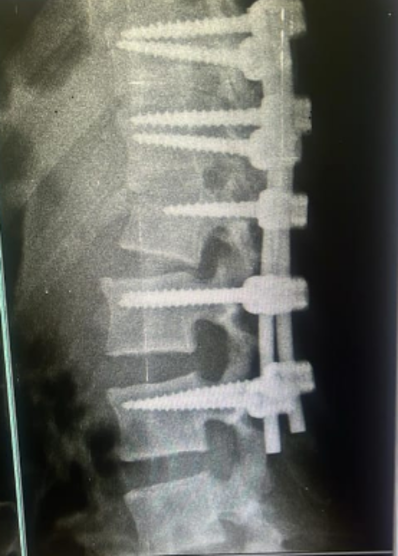

Broken bones are stabilized with screws, rods, or cages to protect the spinal cord and restore alignment.

Stabilization

Rods, screws, or cages are used to restore alignment and protect the spinal cord.